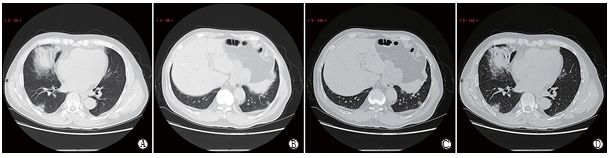

图9 实变期CT影像

男,65岁,发热4 d(体温最高39℃)。实验室检查,WBC:3.72 × 109 /L( 减低), LYMPH:0.90 × 109 /L( 减低), PCT:0.10 ng/ml(升高),CRP:53.0 mg/L(升高);低蛋白血症[TP:62.2 g/L(减低),ALB:35.7 g/L(减低)]、肝功异常 [ALT:79 U/L (升高),AST:72 U/L(升高)]、轻度贫血[RBC:4.10×1012/L (减低),HGB:131.1 g/L(减低),HCT:39%(减低)]。影像学检查,CT表现为右肺中叶、下叶后基底段及左肺下叶外基底段多发斑片状和大片实变、内见充气支气管征象。

图10 消散期CT影像

女性,79岁,间断发热6 d,综合治疗3 d后,实验室检查, RBC:3.73×1012/L(减低)、HB:107g/L(减低),HCT%:31.8(减低),LYMPH%:13.9(减低),LYMPH:0.62×109/L(减低),EO%:0(减低)、EO:0(减低),ALT:46U/L(升高),TP:56.8g/L (减低),ALB:33.5g/L(减低),CRP和PCT正常。A. CT示左肺上叶舌段斑片状磨玻璃密度影及网格状小叶间隔增厚和右肺中叶及 下叶背段斑片状实变影;B.9d后复查CT右肺中叶病变吸收、右肺下叶病变范围缩小、左肺上叶舌段病变吸收呈条索影样变。